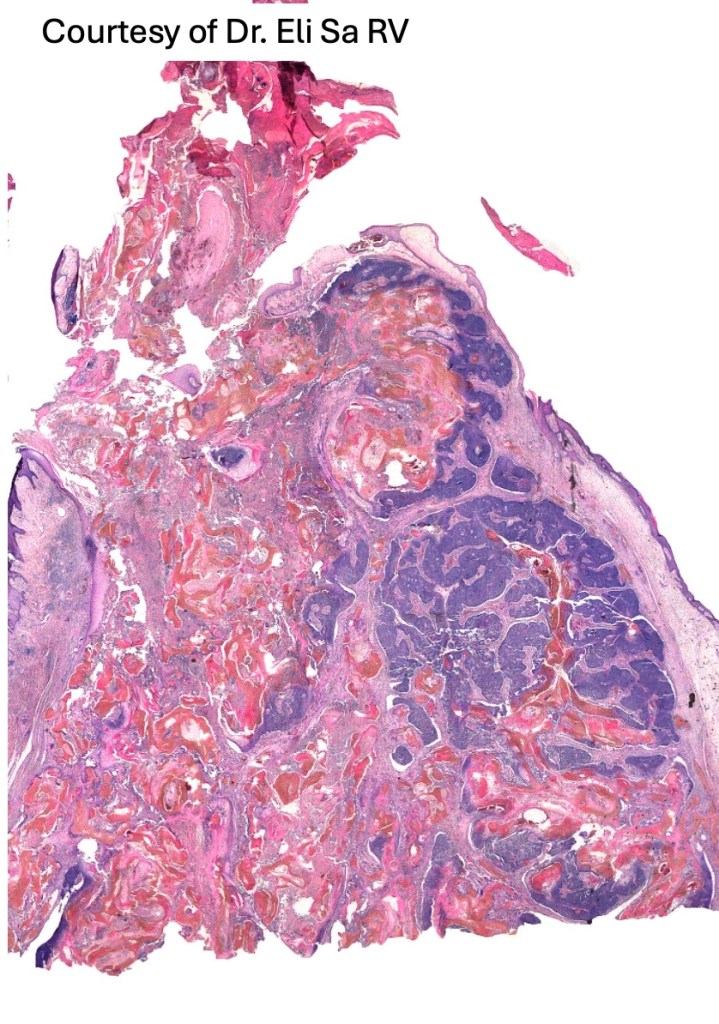

•Multilobulated tumor in dermis +/- subcutaneous fat with a fibrous pseudocapsule

•Basophilic small cells which transition towards supramatricial (orange staining) and ultimately ghost cells with intensely eosinophilic cytoplasm

•Late features include calcification and bone formation

•Foreign body reaction

•Exceptional pseudocystic variant (tumor islands within a cystic cavity)